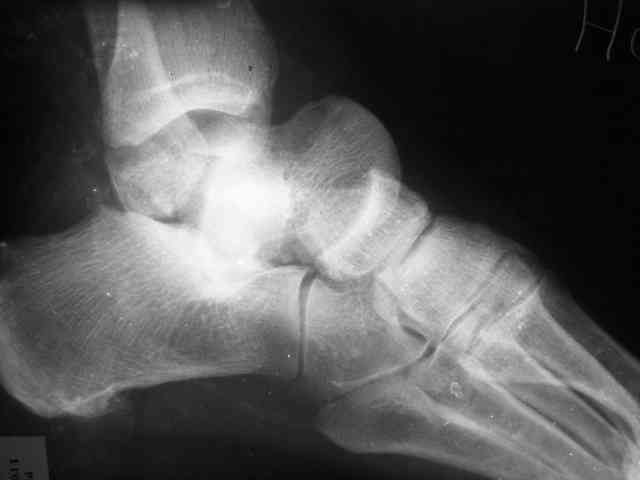

Re: Редкое повреждение - полный вывих тарана!

Уважаемый Александр! Как обещал представляю Р-граммы и операционные фото.

Ваши (лично ваши) рекомендации - астрагалэктомия-аппаратный пяточно-большеберцовый артродез с одновременным удлинением голени - правильно?

А так инфекция куда денется, или ПБА изничтожит ее в м/тканях? Она там уже полгода живет. Я думаю стабильная фиксация - лучшая профилактика инфекционных осложнений. Кстати была у нас больная с посттравматическим деф. артрозом г/стопного сустава и остеомиелитом внутренней лодыжки - ей сделали костно-пластический артродез по Кловарду - инфекция затихла, анкилоз наступил за 3 мес (больной 65 лет).